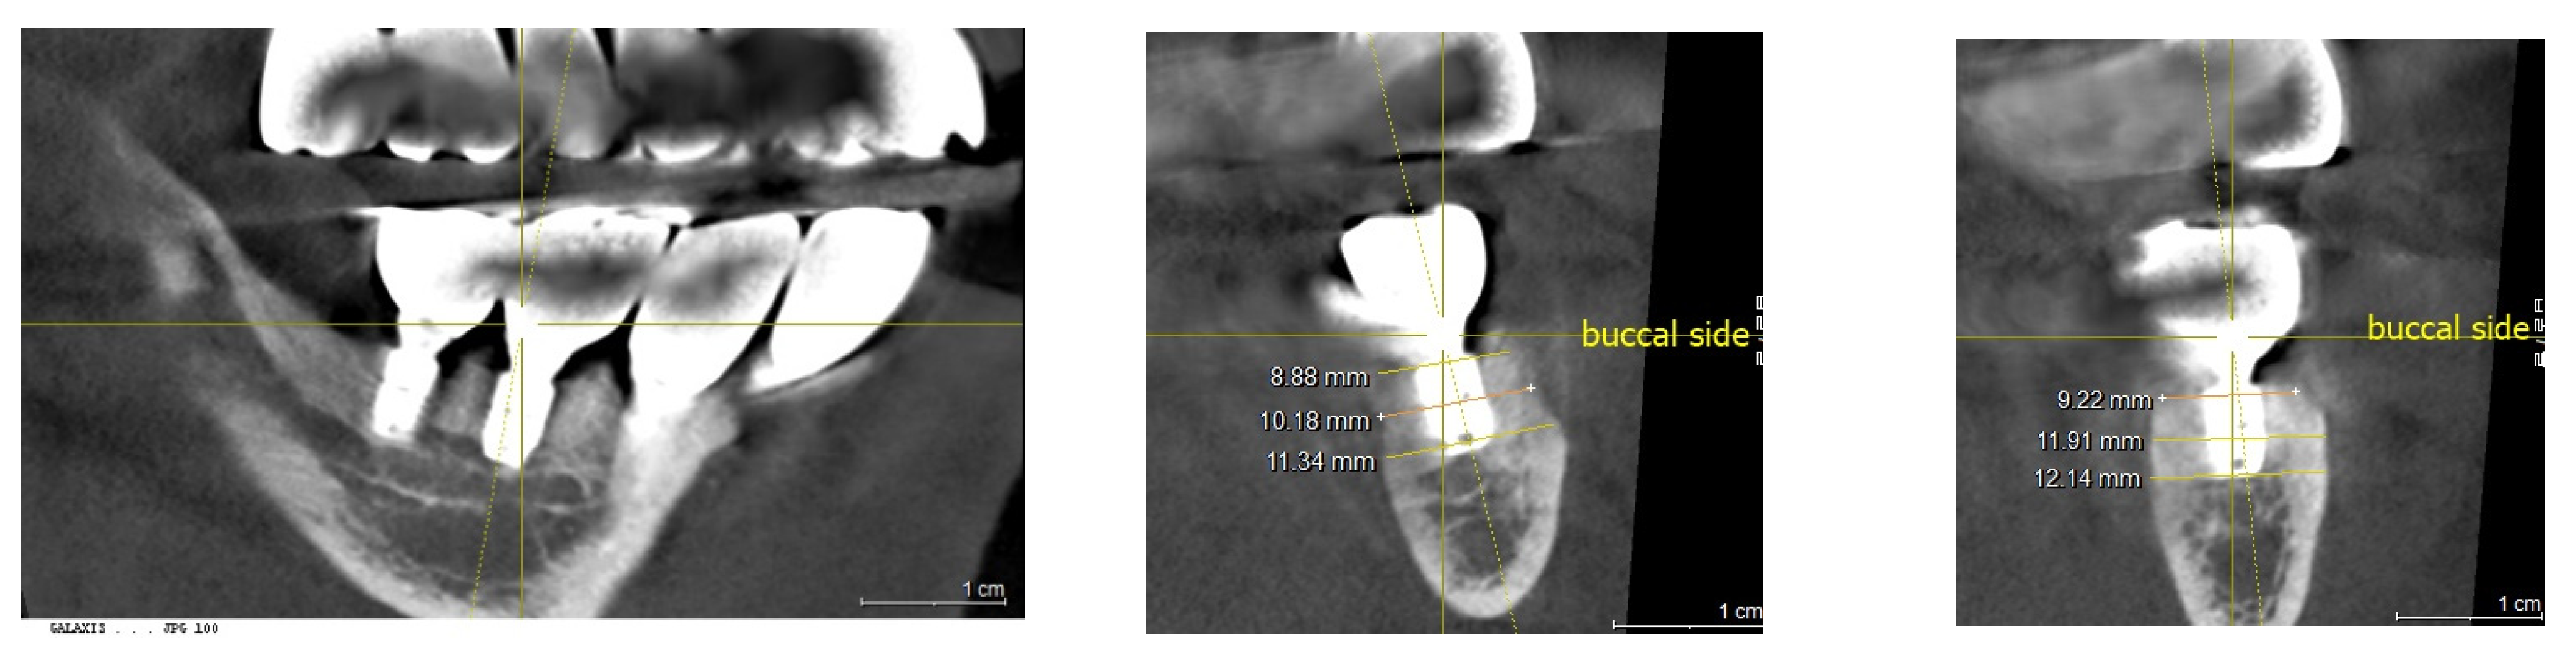

The horizontal width measurements at the crestal level showed 8.9 mm at Point A and 9.2 mm at Point B. Deeper, at the middle level, the measurements increased to 10.1 mm and 11.9 mm, respectively, indicating a substantial growth in bone width crucial for implant support. The peak horizontal bone augmentation reached was 11.9 mm, signifying notable enhancements in the dimensions vital for successful implant placement (Figure 12).

Figure 12. Illustrating the horizontal width measurements at the crestal level, showing 8.9 mm at Point A and 9.2 mm at Point B. Further down, at the middle level, the measurements increased to 10.1 mm and 11.9 mm, respectively, demonstrating a sufficient bone width necessary for implant support.